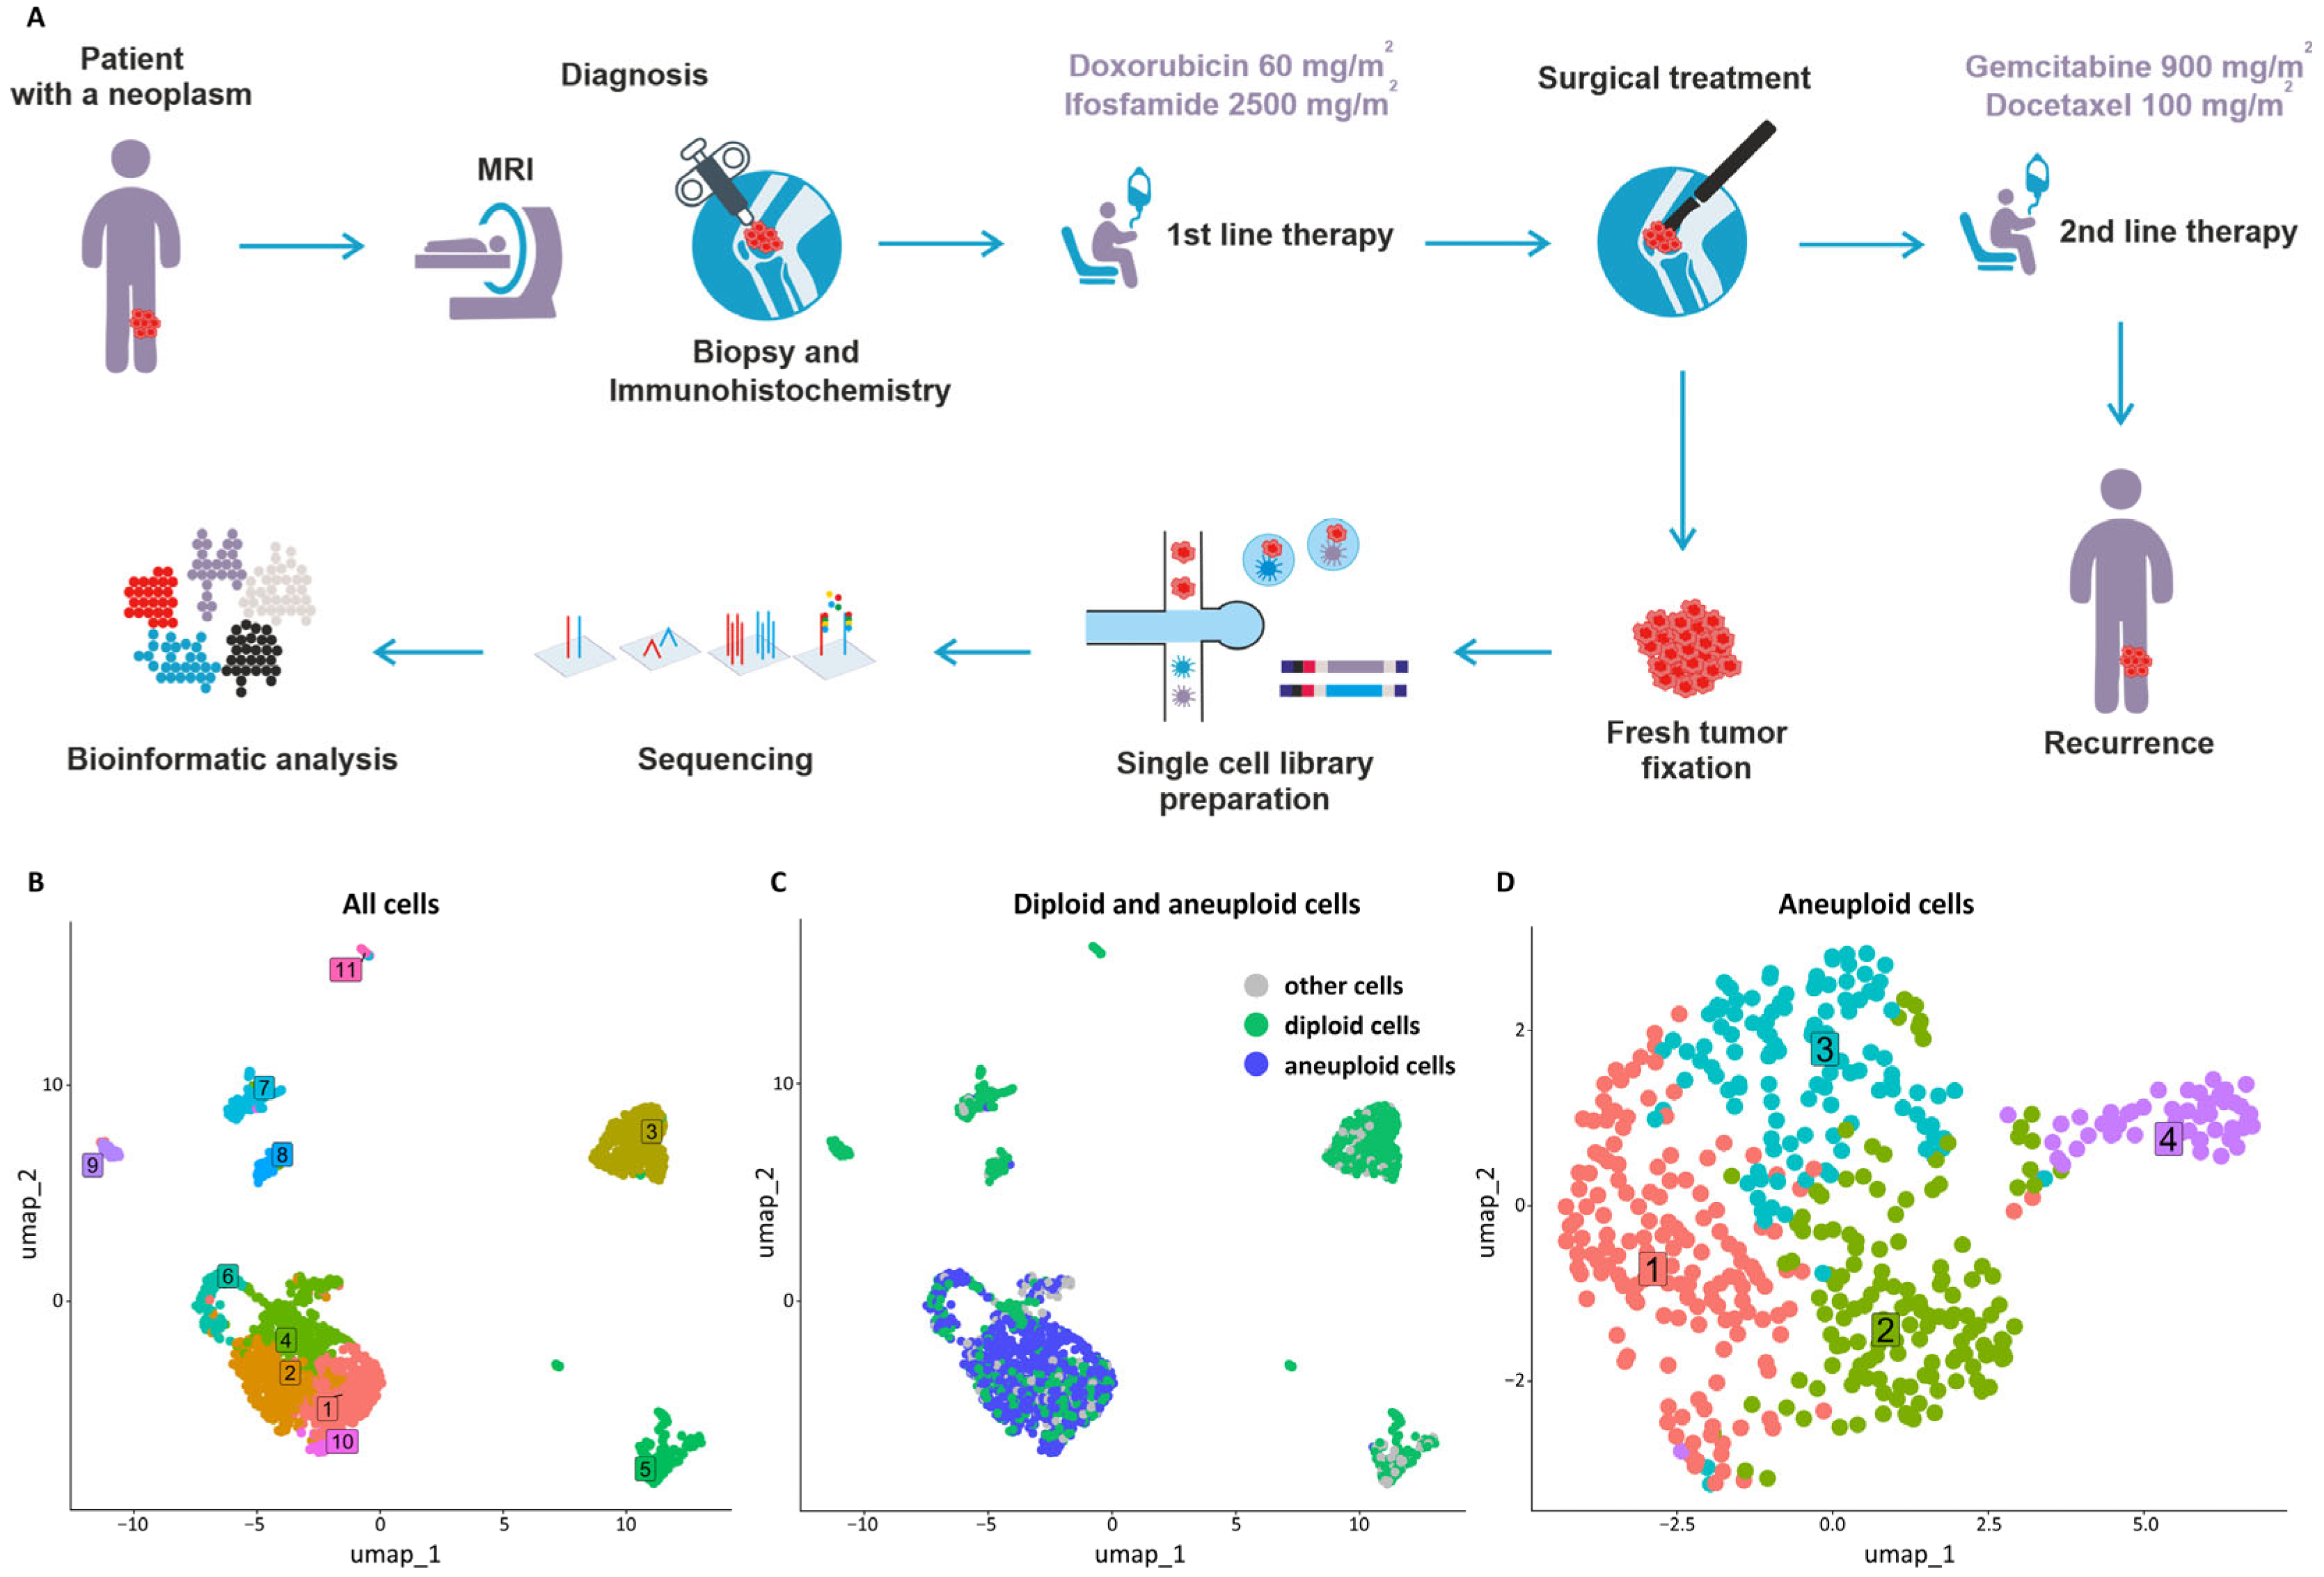

2. Case Report

3. Discussion